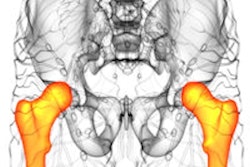

Axial images at L1 level, without (left) and with (right) segmentation overlay. Red indicates skeletal muscle, green indicates trabecular bone, yellow indicates visceral fat, and blue indicates subcutaneous fat. Segmented regions also include liver (beige) and spleen (orange), which were not evaluated as part of present analysis. (A) 78-year-old woman who underwent abdominopelvic CT at an outside institution. Bone tool returned L1 vertebral body bone attenuation of -146 Hounsfield units (HU), outside of reference range. Thus, the tool was deemed technical failure for bone tool. Failure was attributed to volume averaging of vacuum phenomenon within slice. (B) 64-year-old woman who underwent abdominopelvic CT at an outside institution. Bone tool returned vertebral body bone attenuation of -10,000 HU (default value for segmentation failure detected by tool), outside of reference range. Thus, the tool was deemed technical failure for bone tool. Failure was attributed to the presence of spinal fusion hardware. Images and caption courtesy of the American Journal of Roentgenology.The group reported that the three automated AI tools for measuring body composition were technically adequate in 97.7% of the CT exams. The failure rate was 2.3%, and these failures were primarily (88%) due to an image processing error caused by incorrect DICOM header voxel dimension information (i.e., an anisometry error).